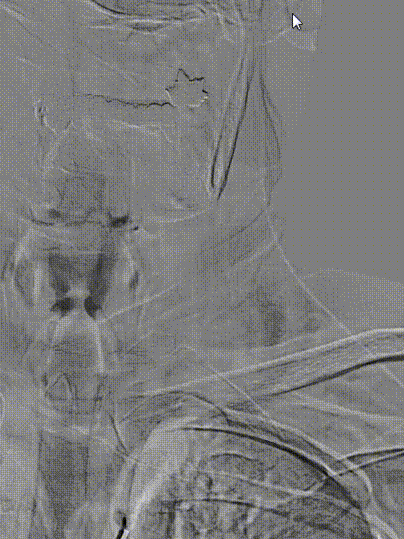

患者取平卧位置,常规消毒、铺巾和局麻右侧腹股沟下穿刺点后,穿刺置入5F动脉鞘,再以5F单弯行选择性脑动脉造影。造影示:II型主动脉弓,右侧颈内动脉C1段重度狭窄。

左侧颈动脉未见明显异常。

造影显示左侧椎动脉V1段中重度狭窄。